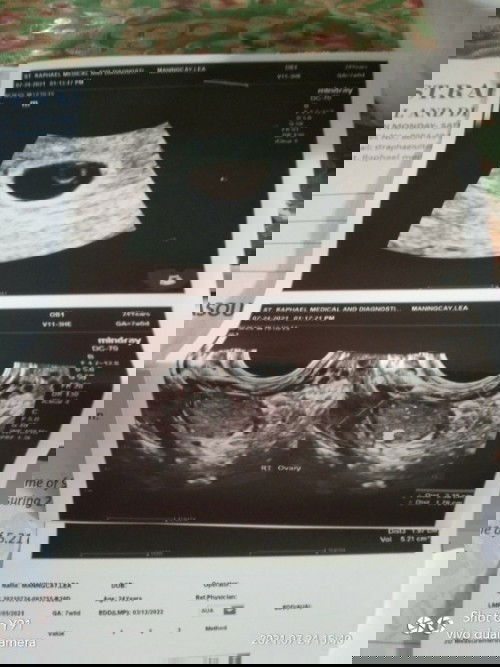

Transvaginal result 😍

This is my transvaginal result i am also done to my pre-natal check up. my OB said i need to take medicine like 3 vitamins for myself and specially to my baby πŸ’™ #firstbaby #1stimemom